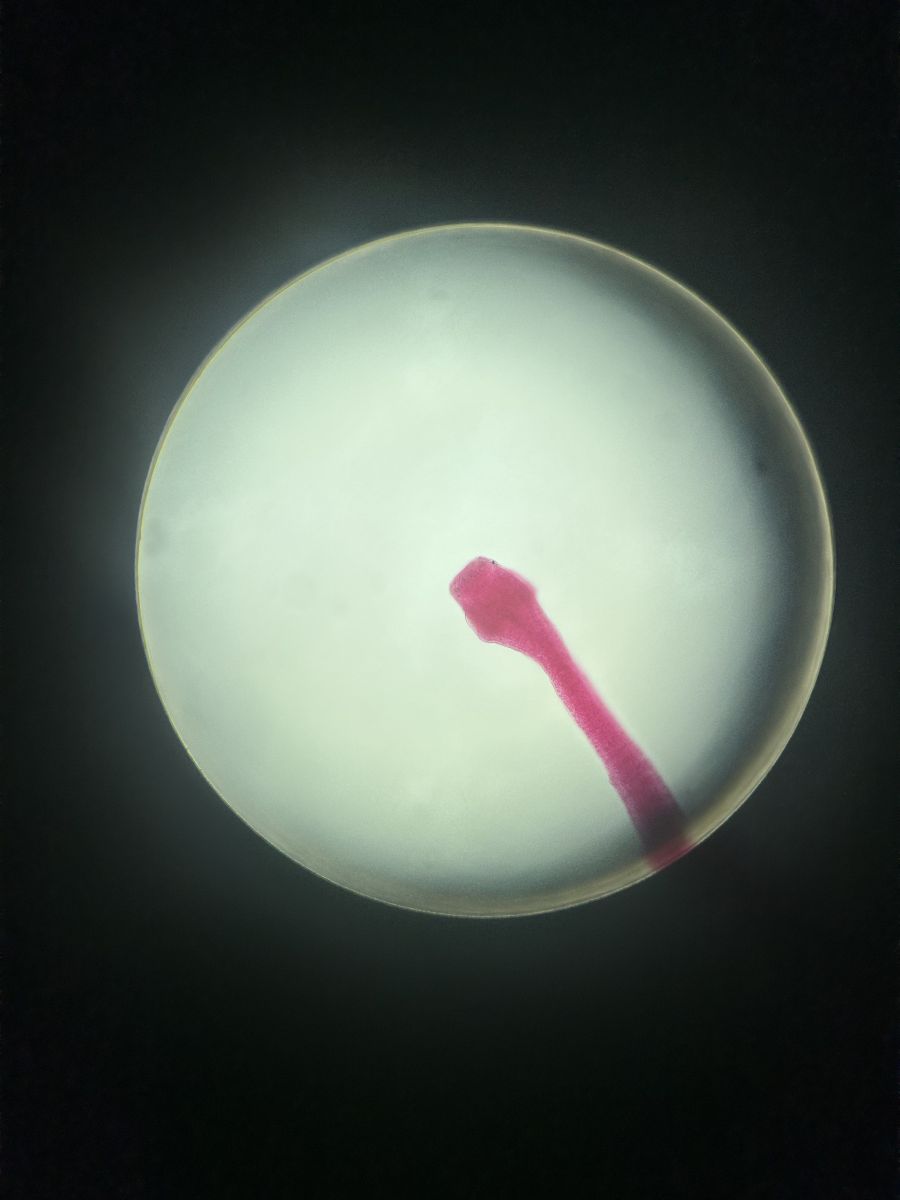

uczestniczyć w niezwykle ciekawych zajęciach w Zakładzie Biologii i Farmakognozji UMB. Podczas krótkiego, ale bardzo interesującego wykładu poznali cykle rozwojowe pasożytów, a następnie przenieśli teorię w praktykę, obserwując liczne preparaty mikroskopowe. Uczniowie oglądali m.in. lamblię, rzęsistka pochwowego, jaja tasiemca i glisty ludzkiej, wągry oraz główkę tasiemca uzbrojonego. Duże zainteresowanie wzbudziły również preparaty formalinowe tasiemca oraz wągra bąblowca.